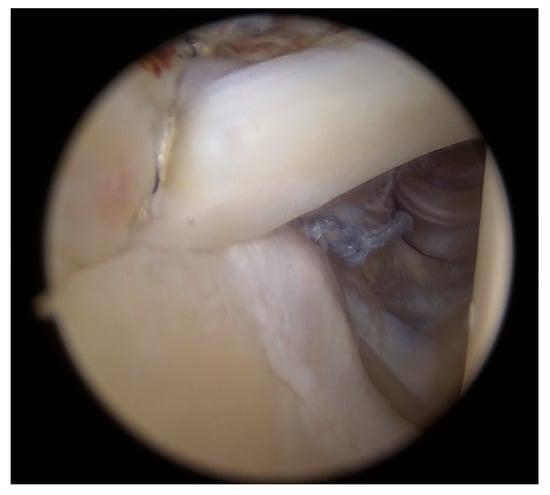

All procedures were performed by the senior author with patients positioned in the beach chair position under general anesthesia. This position was preferred over the lateral decubitus position because it keeps the shoulder in its natural alignment, similarly to in everyday activities, and prevents excessive stretching of the surrounding structures. This allows tendons to be placed over the footprint under natural tension, reducing the risk of overstretching, which could lead to weakness in abduction or early re-tearing, particularly in cases with highly degenerated tendons. The subacromial space is no larger than in everyday activities, like it would be in traction devices, enabling us to standardize the amount of acromioplasty. At the end of treatment, during surgery, the arm is free to be moved in any direction necessary for good visualization of the tear, mostly through rotations. An additional venous line was placed in the contralateral arm to harvest venous blood free of drugs and infusion solutions. The procedure began with the establishment of a standard posterior portal, followed by a thorough standardized intra-articular inspection to confirm MRI and clinical findings. Common intra-articular pathologies, such as SLAP 2 tears or degenerative lesions of the long head of the biceps (LHB), with or without subscapularis tendon involvement, were addressed accordingly. The standard anterosuperior approach was used for debridement of the superior glenoid, tenotomy of the LHB and suture management for the subscapularis or LHB tendon, if necessary. A superolateral portal was carefully positioned to facilitate both SLAP repair and later supraspinatus reconstruction. The SLAP 2 lesion was first cleared of fibrous tissue, and the superior glenoid was debrided to the cortical bleeding bone using a motorized shaver. Through the superolateral portal, a double-loaded titanium CorkScrew Anchor 5.0 (Arthrex, Munich, Germany) was placed slightly posterior to the origin of the long head of the biceps, with sutures passed and tightened in a horse-saddle manner—one posterior and one anterior to the LHB origin (Figure 1)—while subscapularis repair and LHB tenodesis were performed via a direct anterior approach using a similar debridement and scarification protocol, securing the tendon with extra-articular knots.

Figure 1.

Positioning of the sutures.